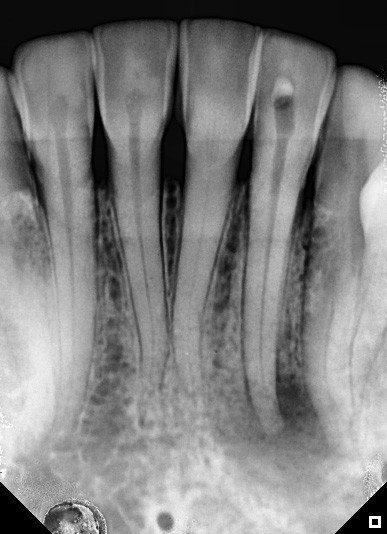

1-Year Follow-Up showing the complete healing of the periapical lesion on teeth #11 and #12

Tooth #11 with a calcified canal following traumatic injury

Treatment of chronic apical abscess

Apical abces in one visit treatment